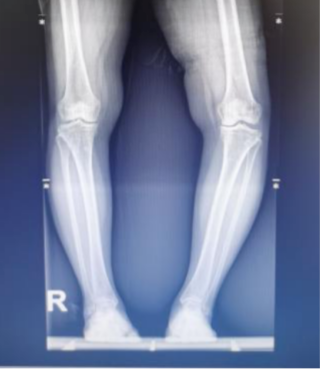

患者术前外形

下肢全长X线,左侧严重内翻畸形